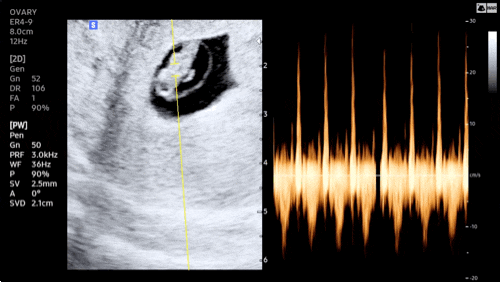

[임신 12주차]증상,드디어 첫 정밀초음파, 성별❣️

엘디와 함께한지 벌써 12주 째! 안정기 시작으로 불리우는 주수이고 나는 드디어!!! 크녹산과 이별했다~~~ ...